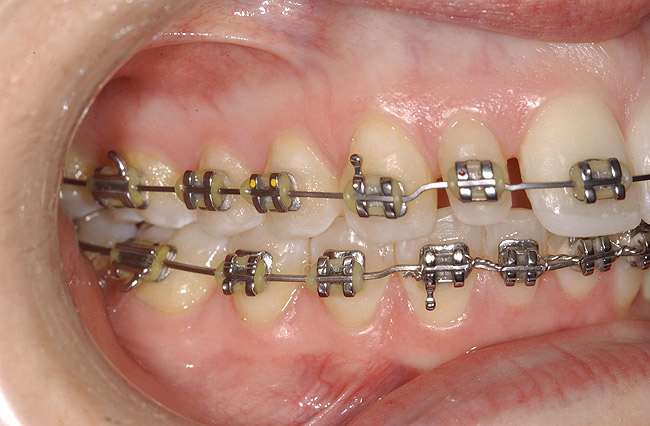

Figure 12  Right buccal view showing posterior occlusion established, canine guidance and proper space appropriation around peg lateral tooth No. 7, and intruded worn incisors.

Figure 12